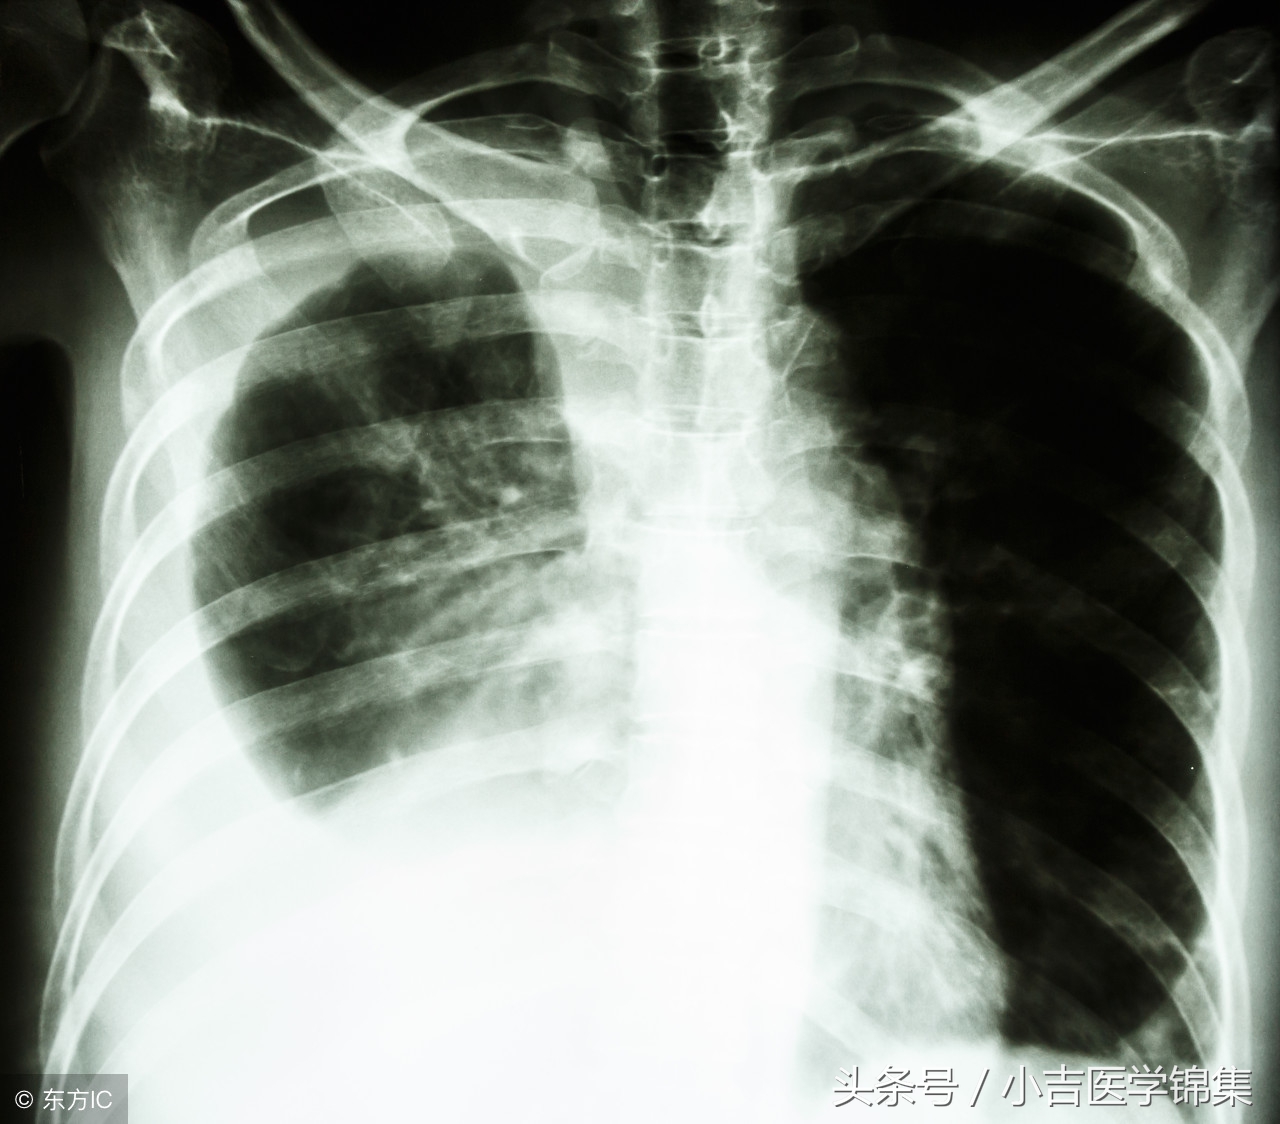

1、胸部X线:在胸片上判断胸腔积液的标准为:在第4前肋间以下为少量胸腔积液,第4前肋与第2前肋之间,属于中等量胸腔积液,积液位于第2前肋以上者,为大量胸腔积液。

⑴较小量积液:胸部x线检查不易发现。

⑵积液量300-500ml,可出现肋膈角变钝。

⑶积液量>500ml,表现为凹面向上,外侧高内侧低的弧形积液影。

⑷大量胸腔积液:整个患侧胸部呈致密影,纵隔和气管向健侧偏移。

⑸包裹性积液:可发生于胸腔任何部位,以叶间积液多见,呈梭形,不随体位改变而变动,边缘光滑饱满。